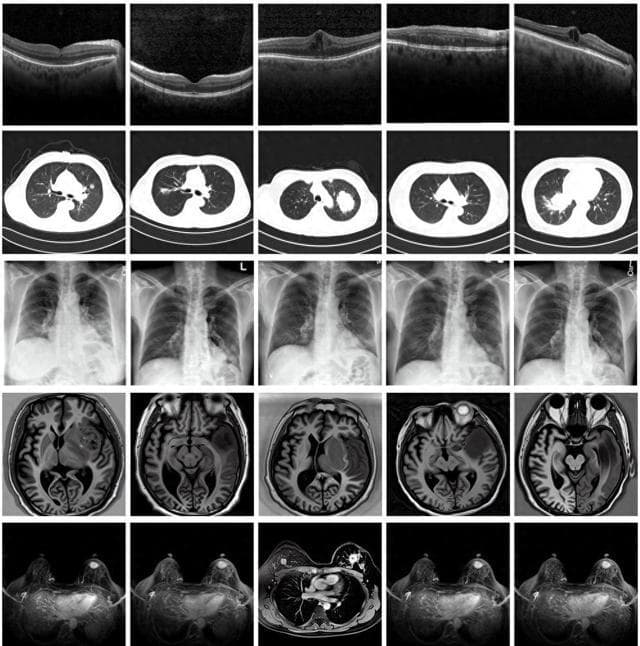

图为由MINIM生成的高质量医学合成图像(受访者供图)

“目前公开的医学影像数据非常有限,我们建立的生成式模型有望解决训练数据不够的问题。”北京大学未来技术学院助理研究员王劲卓说,研究团队利用多种器官在CT、X光、磁共振等不同成像方式下的高质量影像文本配对数据进行训练,最终生成海量的医学合成影像,其在图像特征、细节呈现等多方面都与真实医学图像高度一致。

实验结果显示,MINIM生成的合成数据在医生主观评测指标和多项客观检验标准方面达国际领先水平,在临床应用中具有重要参考价值。在真实数据基础上,使用20倍合成数据在眼科、胸科、脑科和乳腺科的多个医学任务准确率平均可提升12%至17%。